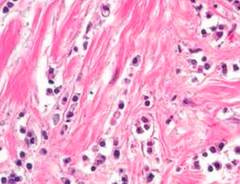

Seminoma

Malignant germ cell tumor of oocytes...similar to dysgerminoma Histology: - large cells with clear cytoplasm and central nuclei (fried egg) - HOMOGENOUS mass with no hemorrhage/necrosis *Good prognosis TM: b-hCG (maybe)